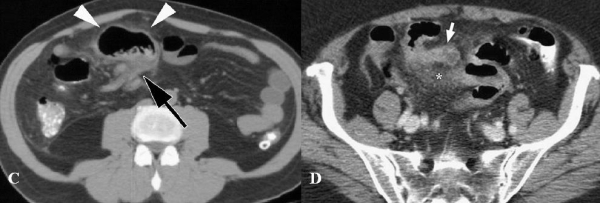

Hình 27: viêm túi thừa Meckel. A, Hình CT tiêm và uống thuốc cản quang ở bệnh nhân nam 22 tuổi, thấy cấu trúc hình ống, thành bắt cản quang, lòng chứa đầy dịch nằm dưới rốn ( mũi tên). Dày thành ruột non kế cận và thay đổi do viêm của mỡ mạc treo. B, CT cản quang tĩnh mạch ở bệnh nhân 49 tuổi, thấy cấu trúc tròn chứa dịch, bắt quang thành, có sỏi vôi bên trong (mũi tên). Thâm nhiễm mỡ kế cận. C, CT cản quang tĩnh mạch ở bệnh nhân 57 tuổi thấy đoạn ruột tận, tròn (đâu mũi tên)dính với đoạn xa hồi tràng (mũi tên). D. Bệnh nhân 76 tuổi. Thấy có đoạn ruột tận, bắt nguồn từ đoạn xa manh tràng bên trong chứa đầy dịch (mũi tên),thâm nhiễm mỡ xung quanh (dấu hoa thị). Tất cả sau mổ là viêm túi thừa Meckel. (Hình A, B, C: Angela D. Levy, Christine M. Hobbs (2004). Meckel Diverticulum: Radiologic Features with Pathologic Correlation. RadioGraphics 24:584. Hình D: Alexandra Platon , Pascal Gervaz (2010). Computed tomography of complicated Meckel’s diverticulum in adults. Insights Imaging 1:56).